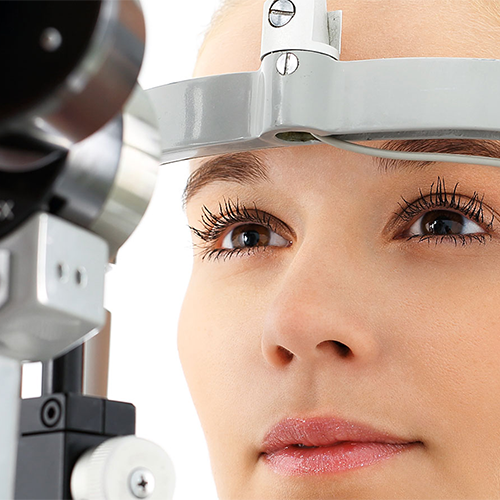

Clínica Oftalmológica Mediterráneo Valencia

Dra. Carmen Tomas Valls

Con una muy amplia experiencia desarrollada en el campo de la oftalmología, el equipo médico de Dra Carmen Tomás, siempre le recibirá en su clínica con un trato amable y personalizado.

En nuestra clínica oftalmológica, encontrará el más avanzado equipo técnico siempre en las manos de reputados y expertos oftalmólogos, que le ofrecerán el mejor y más completo servicio para el tratamiento de todo tipo de enfermedades oculares, así como para la realización de cirugía sin hospitalización.